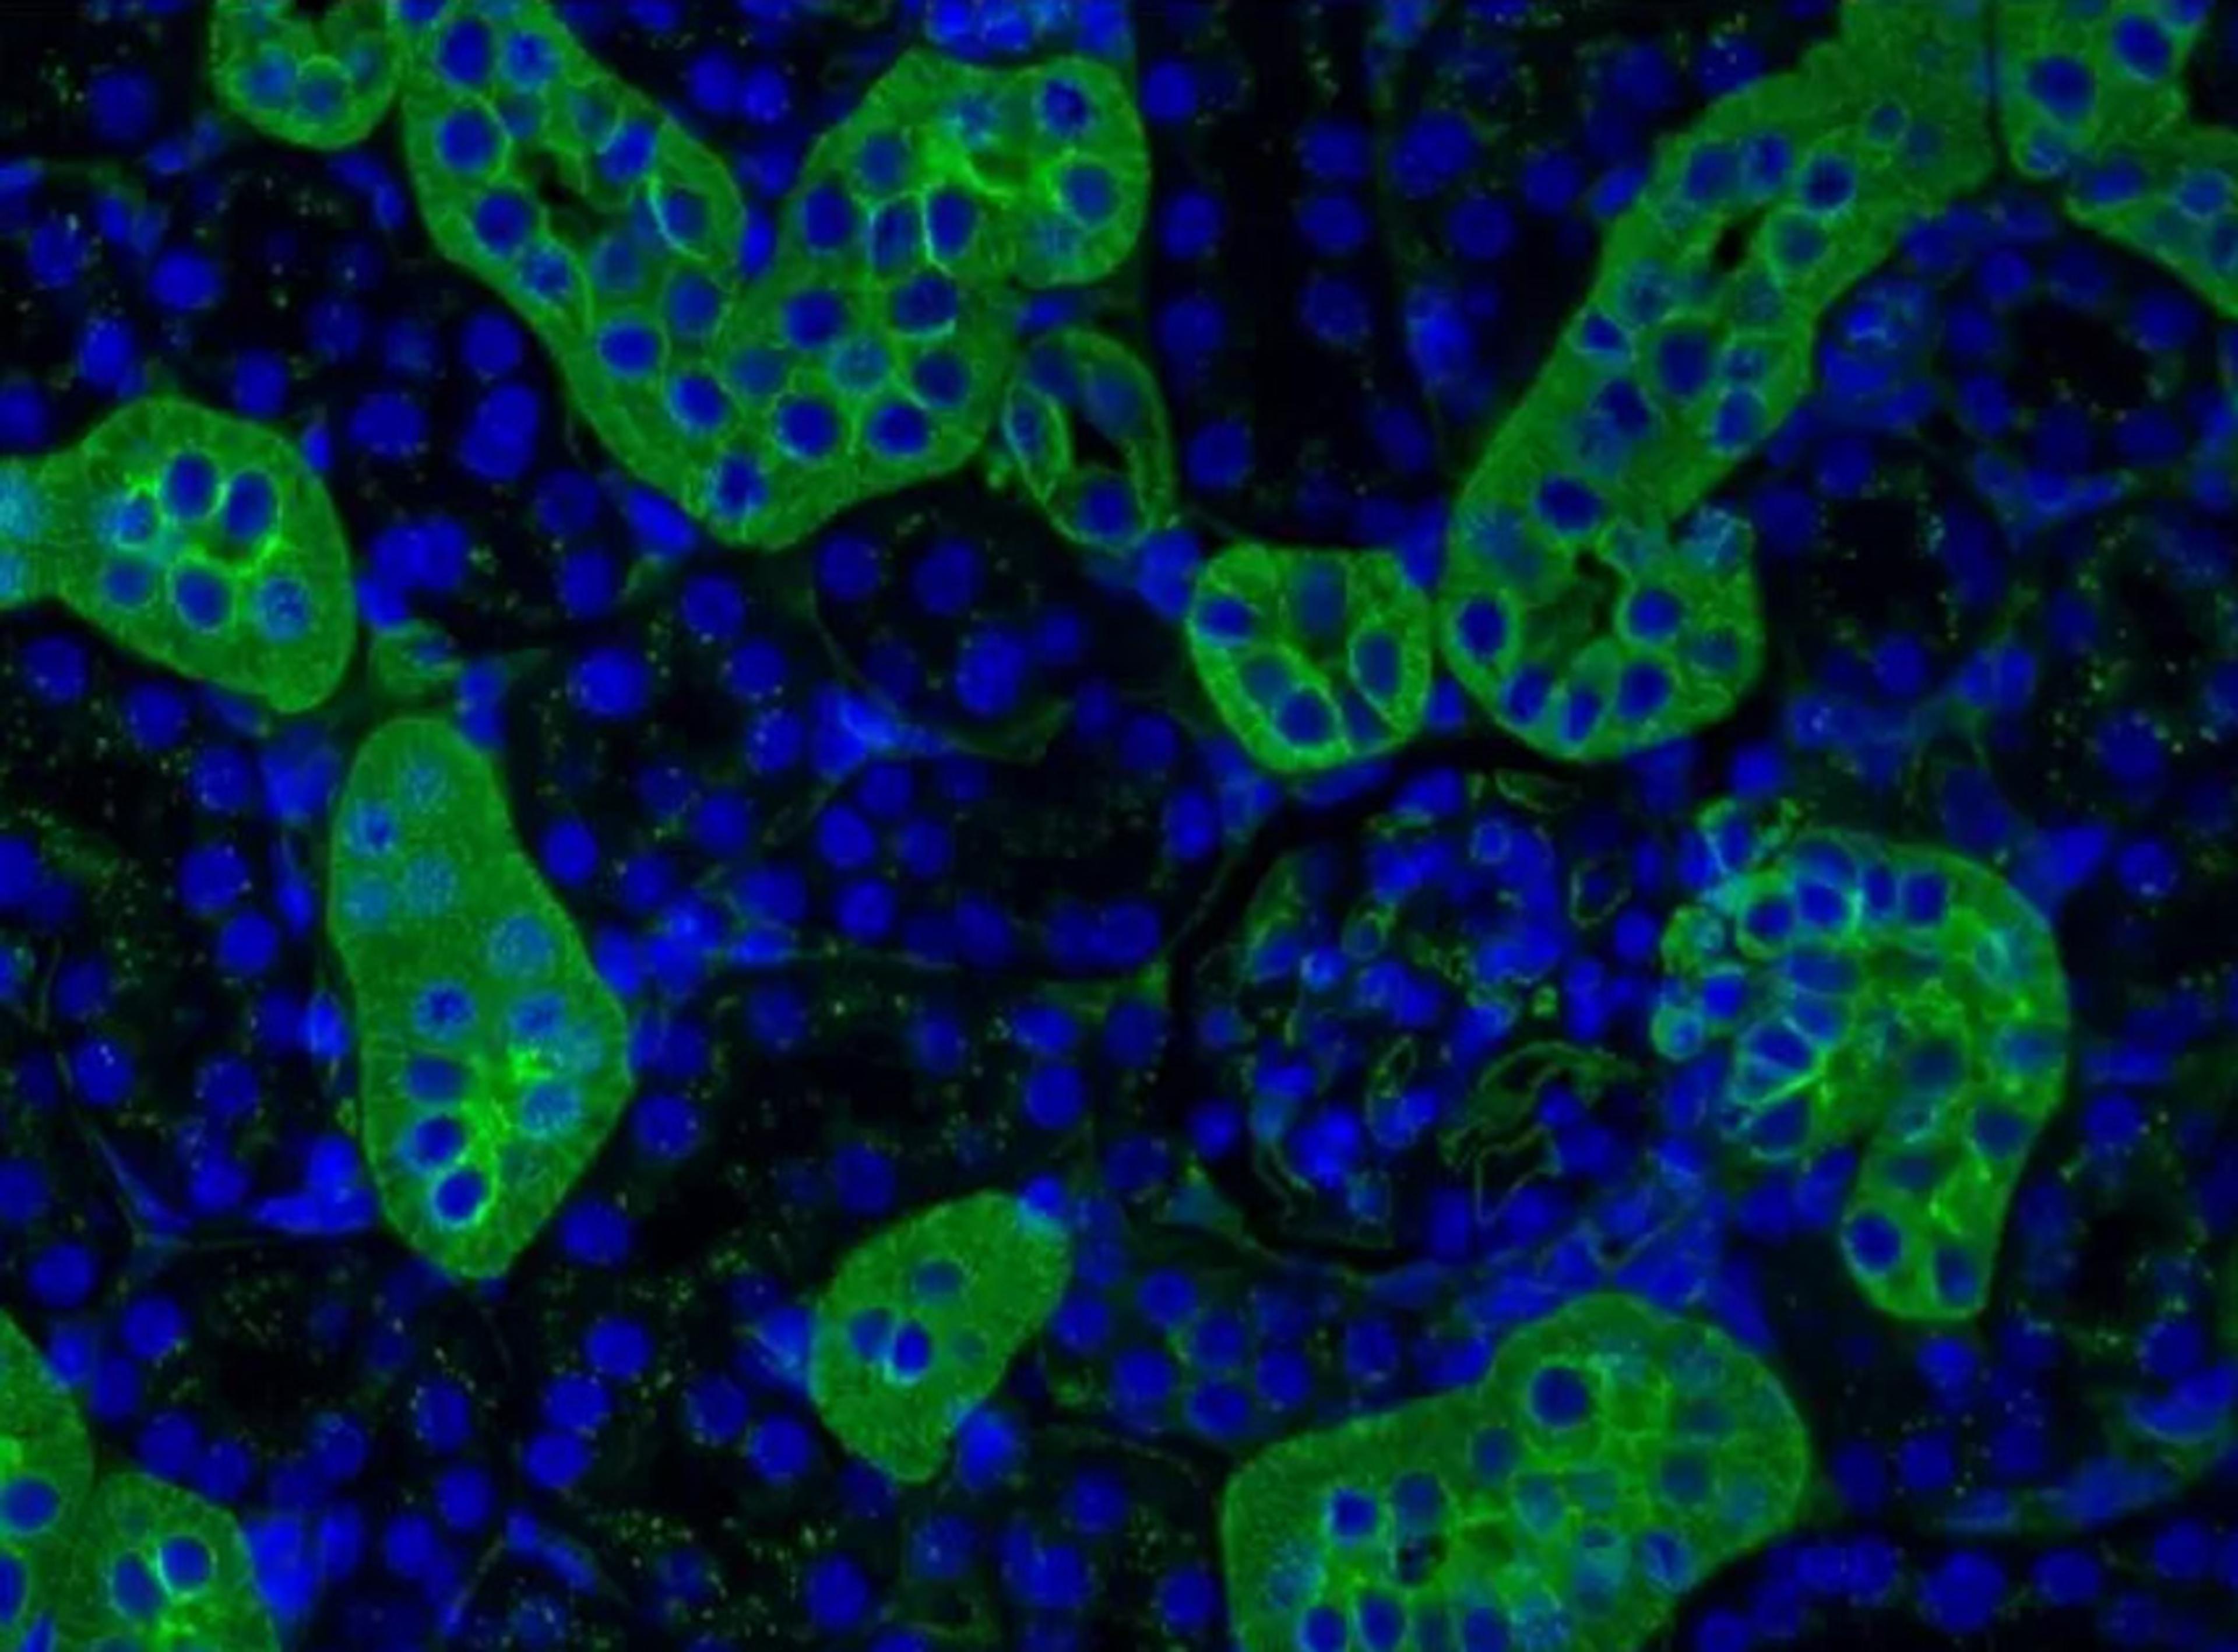

Introduction of a robust workflow for the whole-slide acquisition and co-registration of multiplex immunofluorescence tissue images

In this application note, explore how Indica Labs designed and tested an 8-plex immunophenotyping panel using the InSituPlex® approach to detect and classify T cells, macrophages, and tumor cell in non-small cell lung cancer and colorectal cancer FFPE tissue.

Depicting the cellular architecture of the tumor microenvironment by integrating hyperplex immunofluorescence and automated image analysis

The tumor microenvironment (TME) is emerging as an important factor that shapes the dynamic of tumor growth, heterogeneity, and response to therapies. In this application eBook, Indica Labs focuses on the phenotyping of cells across different tumor types on a tissue microarray (TMA) with an immuno-oncology panel encompassing 20 biomarkers. They interrogated their TME with the use of the COMET™ automated staining and imaging system, and HALO® and HALO AI image analysis platforms.

Qualitative and quantitative evaluation of the tissue microenvironment by high-resolution 17-plex immunofluorescence reveals distinct populations

In this application note, Indica Labs highlights how the use of Orion imaging combined with HALO image analysis provides a powerful and intuitive workflow for visualization and quantification of distinct microenvironment populations.